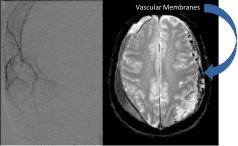

- Brain AVMS